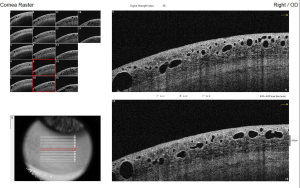

Diagnosis typically involves a detailed eye examination, as well as imaging tests such as ultrasound or anterior segment optical coherence tomography (ASOCT), to evaluate the extent of lymphatic dilation. The hyporeflective lesions vary in size and are cyst-like lesions on ASOCT. [10] Histopathological examination is invasive and confirms the diagnosis.